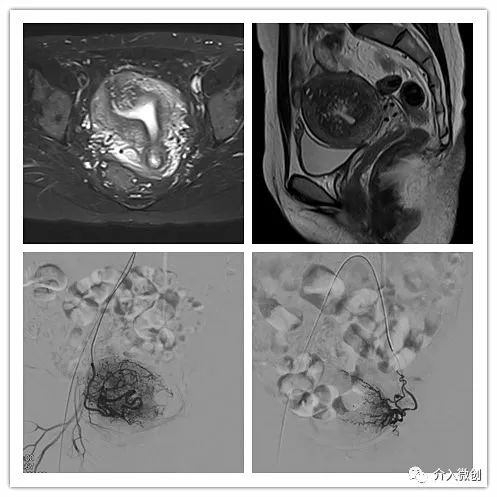

例2

中年患者,患有“子宫腺肌瘤”7年余,长期受痛经、月经量增多折磨,严重影响生活质量。经多处求医,经历药物调理、“曼月乐”宫腔植入、“海扶刀”消融术等多种治疗,痛经、月经量多等情况一直无法得到有效缓解,病情日益严重。

- 术前MRI检查显示子宫明显增大。

术前MRI检查显示子宫明显增大

- 插管至右侧子宫动脉,显示子宫右侧病灶情况

右侧子宫动脉造影

左侧子宫动脉造影

术后复查MRI显示子宫明显缩小,腺肌瘤明显坏死吸收